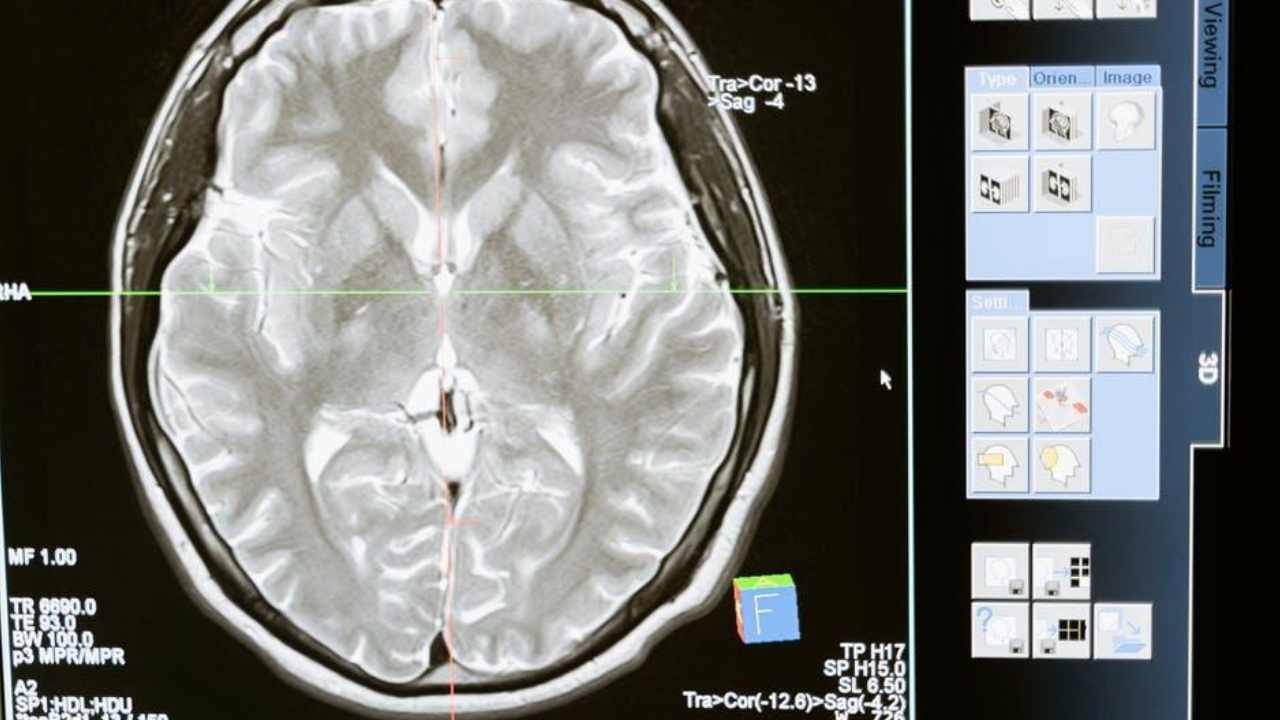

계피의 또 다른 잠재적인 이점은 인지 기능을 향상시키고 신경학적 장애로부터 보호하는 능력이다. 계피는 뇌의 염증을 줄이고, 혈류를 개선하고, 신경 보호 단백질의 생산을 향상시키는데 도움을 줄 수 있는 화합물을 포함하고 있다. 이 모든 것은 건강한 뇌 기능을 도와준다.

의학자들은 계피가 기억력, 주의력, 그리고 전반적인 인지 능력, 특히 노인들에게 이로울 수 있다고 발표했다. 일부 연구는 또한 계피가 노화와 관련된 인지력 저하와 알츠하이머와 파킨슨병과 같은 신경 퇴행성 질환에 대한 보호 효과가 있을 수 있다고 발표했다. 뇌 인지 건강을 위한 계피의 메커니즘과 잠재적인 이점을 완전히 이해하기 위해서는 더 많은 연구가 필요하다. 현재 계피의 항염증 및 신경 보호 특성에 대해 지속적으로 연구가 계속되고 있다.